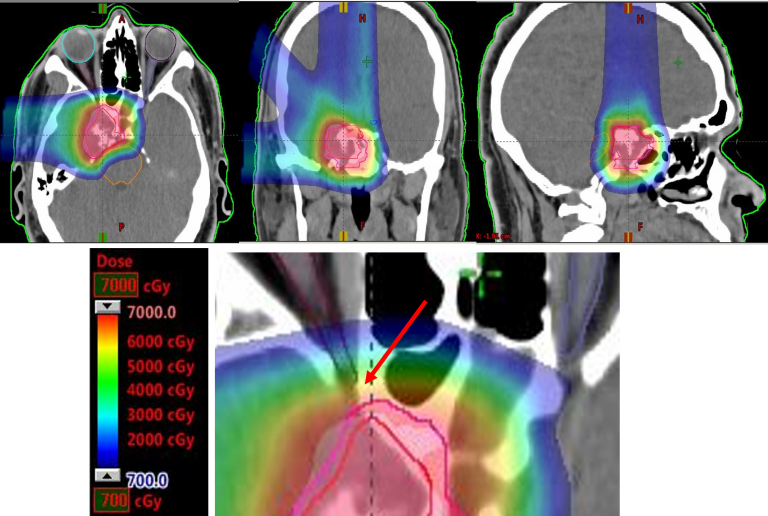

As the protons move through the body, they slow down and interact with electrons, and release energy. The point where the highest energy release occurs is the “Bragg peak.”

A physician can designate the Bragg peak’s location, causing the most damage to the targeted tumor cells.

A proton beam conforms to the shape and depth of a tumor while sparing healthy tissues and organs.

The team at MD Anderson Proton Therapy Center has continued to expand ways to use proton therapy to benefit patients. The team pioneered pencil beam proton therapy, also called scanning beam, and intensity modulated proton therapy (IMPT). The techniques are now available to other treatment centers said Dr Prem Pillay.

Pencil beam technology and IMPT build on the benefits of proton therapy. With a proton beam just millimeters wide, these advanced forms of proton therapy combine precision and effectiveness, offering unmatched ability to treat a patient’s tumor and minimizing the effect on a patient’s quality of life – during and after treatment. They rely on complex treatment planning systems and an intricate number of magnets to aim a narrow proton beam and essentially “paint” a radiation dose layer by layer.

Pencil beam is very effective in treating the most complex tumors, like those in the Brain, Spine,eye, and cancers in children, while leaving healthy tissue and other critical areas unharmed. IMPT is best used to deliver a potent and precise dose of protons to complex or concave-shaped tumors that may be adjacent to the spinal cord or embedded head and neck or skull base below the brain or around brain critical structures.